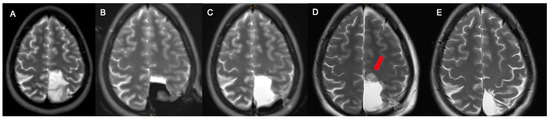

2.2. OR Setup and MRI

- Before surgery: T1 MPRAGE +/− Gadolinium enhancement, T2 SPACE, FLAIR 3D, DWI, PWI;

- Intraoperative MRI: T1 MPRAGE, T2 SPACE, FLAIR 3D, DWI, (+/− Gadolinium enhancement, PWI);

- Intraoperative after additional resection: T1 MPRAGE+/− Gadolinium enhancement, T2 SPACE, FLAIR 3D, DWI, PWI.

2.3. MRI Volumetric Assessment